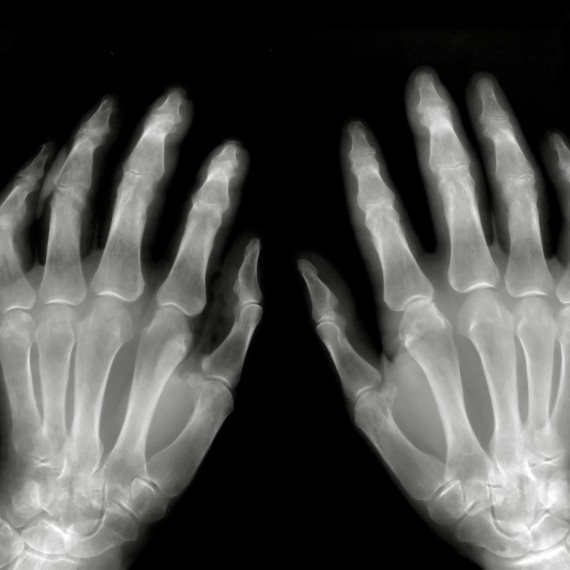

נימול באצבעות

"אני מרגישה נימול בכל האצבעות"

המאזינה בת ה-82 שברה את מפרק היד לפני מספר חודשים וכעת מרגישה נימול באצבעות • האם עליה לעבור ניתוח?